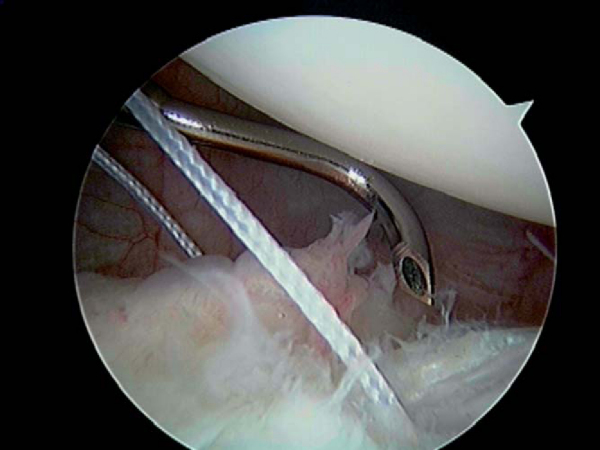

| • | Once the capsule is pierced through, a No. 1 polydioxanone (PDS) suture (Ethicon, Inc., Somerville, NJ) is shuttled into the joint and the penetrator is removed ( Fig. 9-4 ). |

|